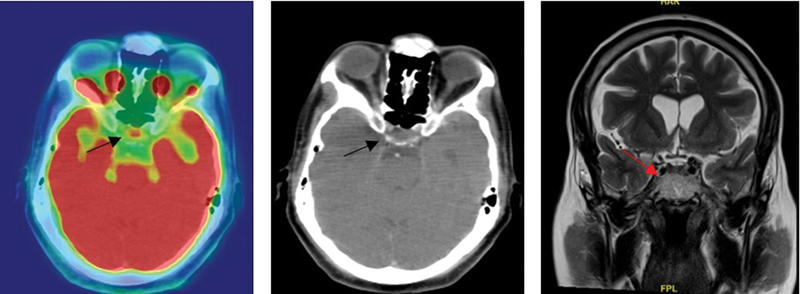

Introduction  Pituitary adenoma is the most common disease that affects the gland and may be classified as functional/nonsecretory tumors. Inflammatory/infective causes may also affect the pituitary gland. The 18F-fluorodeoxyglucose positron emission tomography/computed tomography (F18-FDG PET/CT) may have an incremental value in assessing these lesions and in determining their clinical significance. Aim  This article assesses the utility of F18-FDG PET/CT in detecting and determining clinical profile of pituitary lesions with abnormal uptake. Methodology  Retrospective analysis of all patients who underwent F18-FDG PET/CT from January 2015 to January 2023 was done. Those with abnormal pituitary uptake (standardized uptake value [SUV] > 2.5) were included in the study. SUV value along with relevant anatomical details, biochemical parameters, histopathological details, and follow-up imaging were analyzed. Results  Among 15,085 studies, a total of 36 patients (21 males/15 females, average age 47.36 years, range: 17-75 years) with pituitary uptake (0.23%) were included. Out of 36 patients, causes are primary pituitary tumor (21/36, 58%), tubercular hypophysitis (3/36, 8%), lymphocytic hypophysitis (2/36, 6%), lymphomatous involvement (2/36, 6%), autoimmune hypophysitis (1/36, 3%), questionable significance/incidental (4/36, 11%), and metastasis (3/36, 8%)-one each from neuroendocrine tumor ileum, chondrosarcoma, and adenocarcinoma lung. There was no difference in the SUV range between the different etiologies. Among 21 patients with pituitary tumor, biochemical evaluation was done in 19 patients. Two patients were lost to follow-up and did not have biochemical evaluation. Among them, 8 underwent endoscopic transsphenoidal radical excision and 1 patient had PET-CT-guided stereotactic radiosurgery alone. In another 8 patients who had prior endoscopic transsphenoidal radical excision, uptake was noted as residual lesion on PET-CT. Of them, 3 underwent subtotal excision and 5 had PET-CT-guided stereotactic radiosurgery. Biopsy was done in 14 patients, of which 11 were macroadenoma and 3 were microadenoma. Overall, magnetic resonance imaging (MRI) brain was performed in 22 of them and the findings were concordant with F18-FDG PET/CT. Conclusion  F18-FDG PET/CT is a useful modality in the evaluation of pituitary uptake. It has an incremental value along with MRI brain and biochemical parameters and is useful for follow-up. Due to its high diagnostic accuracy, it is particularly useful in those with suspected residual/recurrent adenomas.